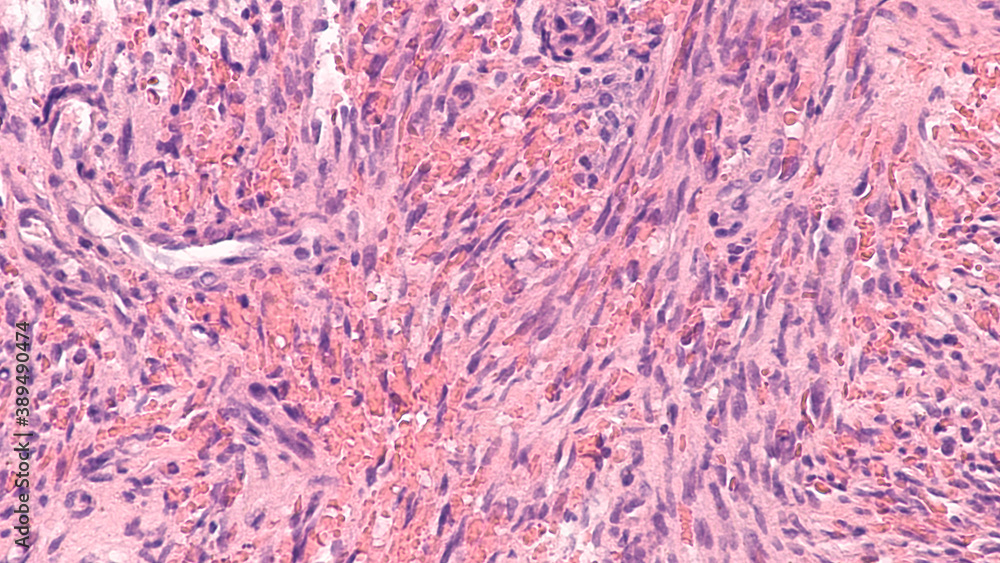

From stock.adobe.com

Kaposi's is a type of cancer of blood vessels caused by a virus Kaposi Sarcoma Caused By Virus kaposi's sarcoma (ks) is an angioproliferative disease, with a viral etiology and a multifactorial pathogenesis. Most people infected with this virus don't get kaposi sarcoma. It affects people with weakened immune systems who also carry the rare virus. kaposi’s sarcoma is caused by a virus called human herpes virus 8 (hhv8). kaposi sarcoma (kaposi’s sarcoma) is a. Kaposi Sarcoma Caused By Virus.

From www.sciencephoto.com

Kaposi's Stock Image M112/0312 Science Photo Library Kaposi Sarcoma Caused By Virus kaposi’s sarcoma is caused by a virus called human herpes virus 8 (hhv8). what causes kaposi’s sarcoma? Most people infected with this virus don't get kaposi sarcoma. But certain people who get this virus are more likely to develop one of the types of kaposi sarcoma: kaposi sarcoma (kaposi’s sarcoma) is a form of soft tissue sarcoma.. Kaposi Sarcoma Caused By Virus.